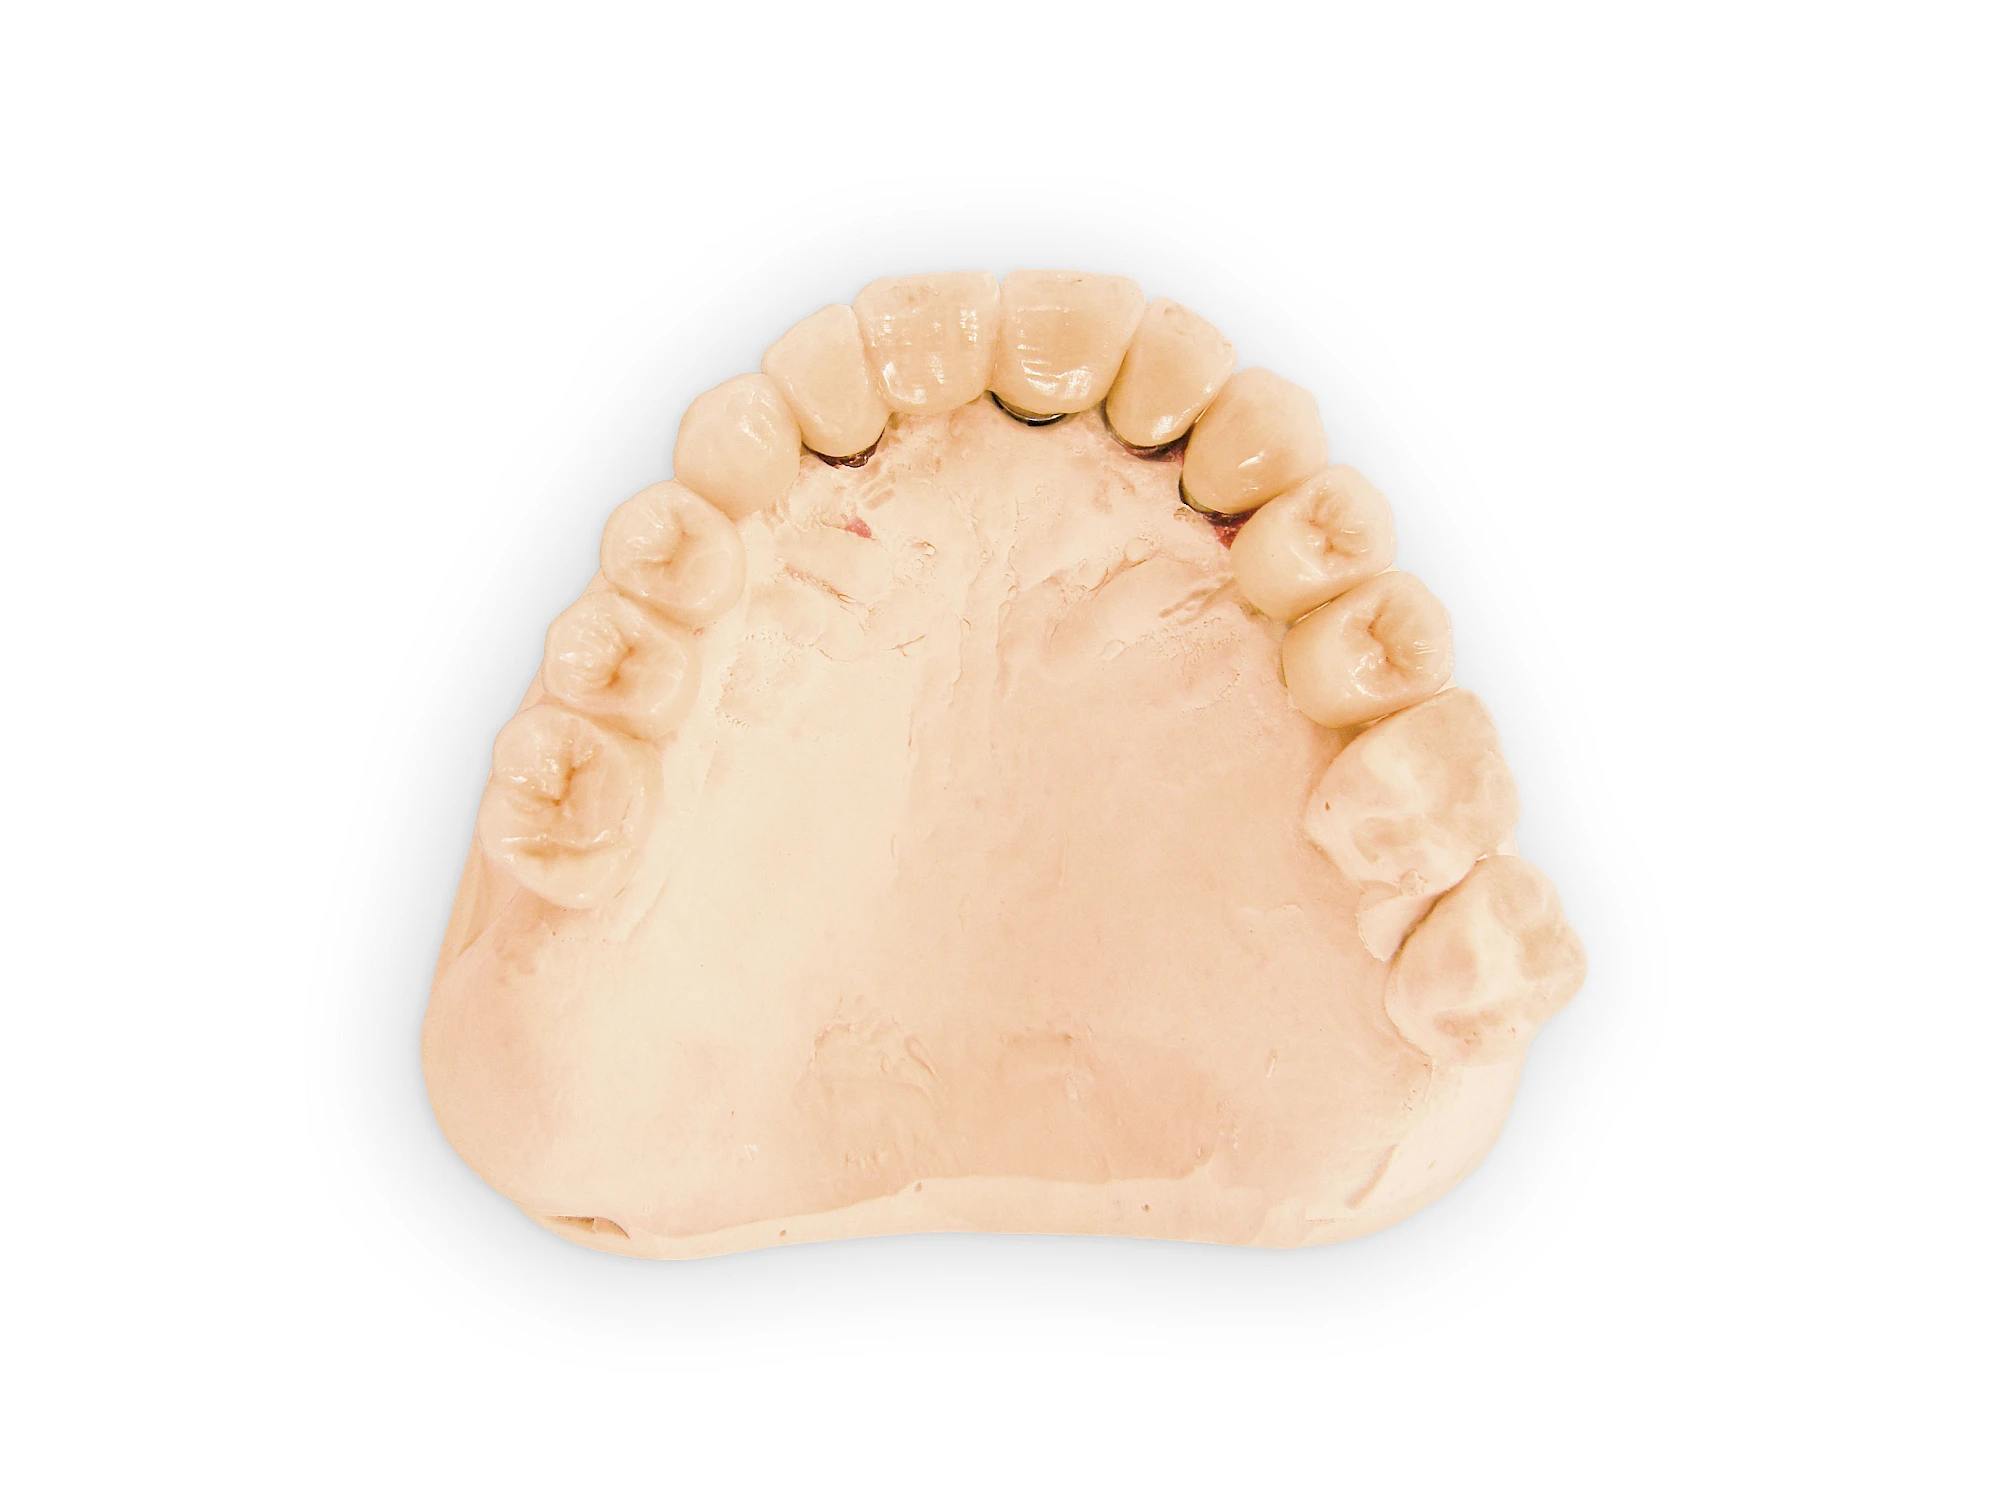

Fehlen einzelne Zähne und die Nachbarzähne sind unbeschadet oder gut zahnärztlich versorgt, werden immer häufiger Implantate gewählt, um die Lücken zu schließen. Auch bei größeren oder verteilten Lücken, wenn keine herausnehmbare Prothese gewünscht ist, werden Implantate für Kronen- bzw. Brückenversorgungen gesetzt. In Einzelfällen entscheiden sich sogar zahnlose Patienten für eine festsitzende Versorgung auf Implantaten.

Varianten zur Verankerung von festsitzendem Zahnersatz auf Implantaten

Implantate: Prothesen

Varianten zur Verankerung von abnehmbarem Zahnersatz auf Implantaten